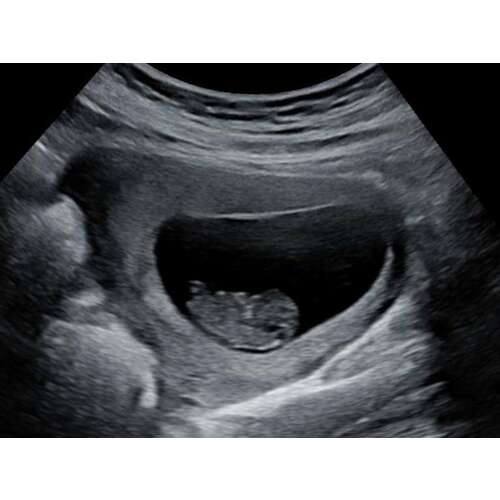

Een verse echo van vanochtend :) 8w5d